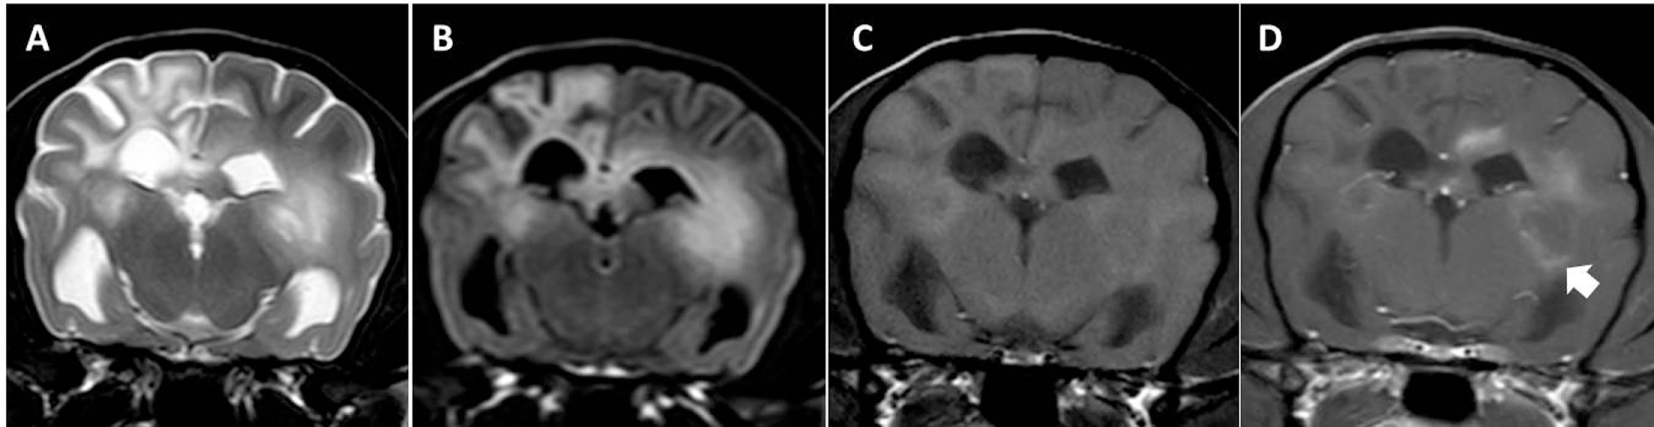

Figure 2. Transverse magnetic resonance images (0.5 T) of a Yorkshire Terrier (3 years, male) with subacute necrotizing encephalopathy. Bilateral symmetric hyperintensities in the cingulate gyrus and in the thalamus on T2-weighted (A) and fluid-attenuated inversion recovery (B) images. These lesions have a hypointense center on T1-weighted (C) images and they do not enhance after a contrast injection (D).

Figure 4. Transverse magnetic resonance images (3 T) of a Pug (3 years, male) with necrotizing meningoencephalitis. Diffuse T2 (A) and fluid-attenuated inversion recovery (B) hyperintensities predominantly on the left in the prosencephalon resulting in the complete loss of cortical gray and white matter distinction. There is a patchy parenchymal and a leptomeningeal enhancement after a contrast injection [(C) T1-weighted native; (D) T1 weighted after contrast injection]. The midline is slightly shifted to the right side caused by the expansion of the prosencephalon on the left-hand side.